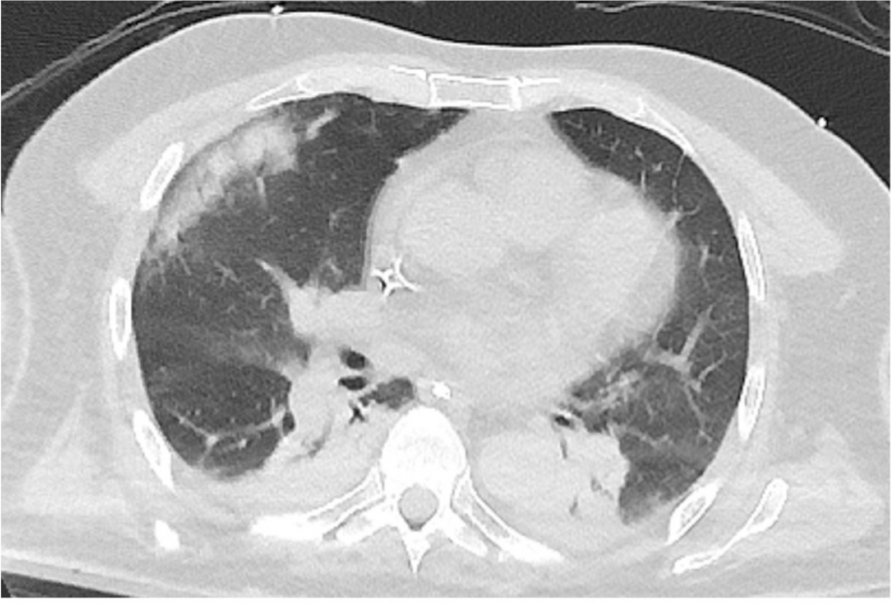

In this specific case, the patient, affected by L. Pneumophila, presented a PO2/FiO2 ratio between 100mmHg and 200mmHg, giving rise to a moderate ARDS panel according to Berlin Criteria (Image 1).

For this reason, we decided to use a non-invasive periprocedural ventilation mode, specifically the High Flow Nasal Cannula (HFNC), to reduce the risk of postoperative pulmonary complications due to invasive ventilation through endotracheal intubation (ETI).

Image 1 (abstract A9).

See text for description